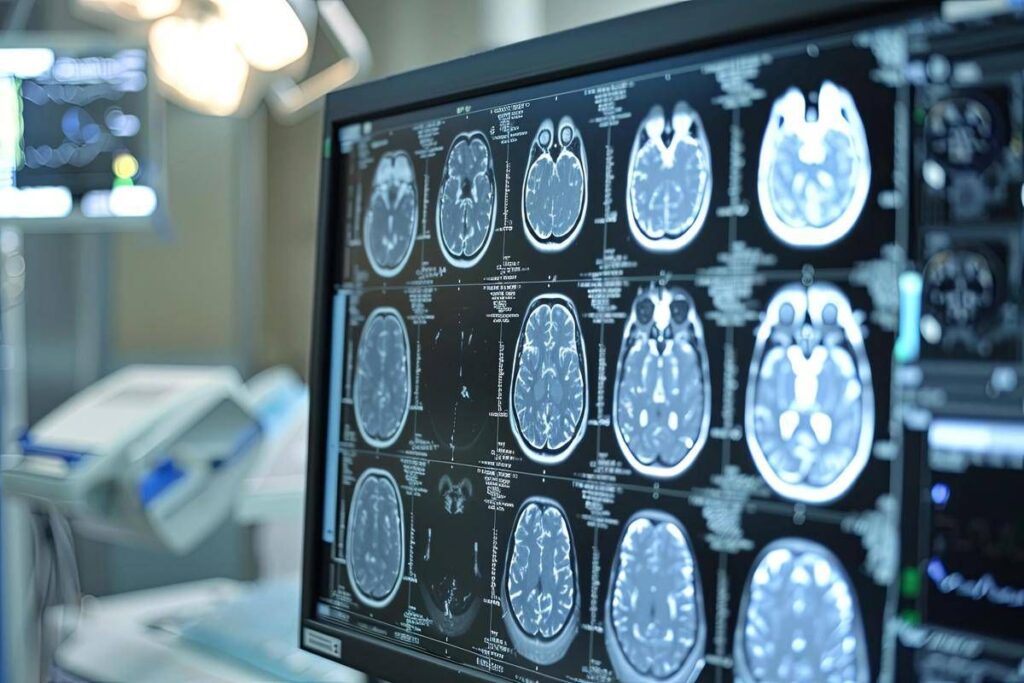

Neoplasie cerebrali, in Italia ogni anno 3mila casi di glioma

“Sono tumori cerebrali molto complessi e che spesso vengono diagnosticati in età giovanile – afferma Saverio Cinieri, presidente di Fondazione Aiom – Si sviluppano da cellule del cervello chiamate gliali e possono avere una prognosi variabile, ma potenzialmente a lungo termine. La gestione della patologia richiede una stretta collaborazione fra neurochirurgo, radioterapista e oncologo medico. Attraverso il bisturi è possibile rescindere la massa tumorale oppure eseguire una biopsia grazie a nuove e sofisticate tecnologie. La radioterapia permette di ridurre il rischio di recidiva o eliminare quella parte di cancro che non è stato possibile rimuovere chirurgicamente. Viene somministrata insieme alla chemioterapia e le sedute sono di solito diluite nel corso del tempo, per limitare l’impatto degli effetti collaterali. Infine, l’oncologo medico deve scegliere i farmaci da somministrare e deve selezionarli valutando le condizioni cliniche del singolo paziente”.

“Anche per il trattamento dei gliomi, in particolare quelli di basso grado, si può ricorrere all’oncologia di precisione che potrà ridisegnare la pratica clinica nel prossimo futuro – illustra Enrico Franceschi, direttore dell’Oncologia del sistema nervoso all’Irccs Istituto delle scienze neurologiche di Bologna – E’ molto importante verificare la presenza o meno delle mutazioni Idh1 e Idh2. Questi biomarcatori indicano specifiche patologie caratterizzate da una prognosi decisamente più favorevole e maggiore sensibilità dei gliomi alla radio e chemioterapia. Al momento della diagnosi è quindi essenziale l’esecuzione precoce di alcuni test molecolari per identificare al meglio i diversi sottotipi di gliomi. Tra le terapie di nuova generazione vi è anche vorasidenib, un farmaco orale inibitore Idh1 e Idh2 che ha dimostrato di essere un trattamento efficace nel posticipare la radio e chemioterapia nei gliomi di basso grado ed è una rilevante innovazione medico-scientifica”.

“Ancora una volta l’oncologia medica è centrale nella gestione multidisciplinare di neoplasie estremamente complesse ed insidiose – sottolinea Franceschi – Il trattamento dei gliomi inizia nel momento della diagnosi che deve essere sia morfologica che molecolare. Esistono infatti 150 diversi sottotipi di neoplasia cerebrale ed è fondamentale riconoscere fin da subito le caratteristiche del singolo caso per poter così selezionare le terapie più appropriate. Fino a pochi anni fa avevamo a disposizione solo chirurgia, radioterapia e chemioterapia. Ora i farmaci ad azione mirata sono una realtà anche nella cura dei tumori cerebrali che esprimano specifiche alterazioni molecolari”.